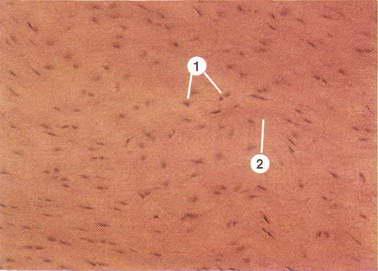

Структура грубоволокнистой костной ткани: наглядные примеры